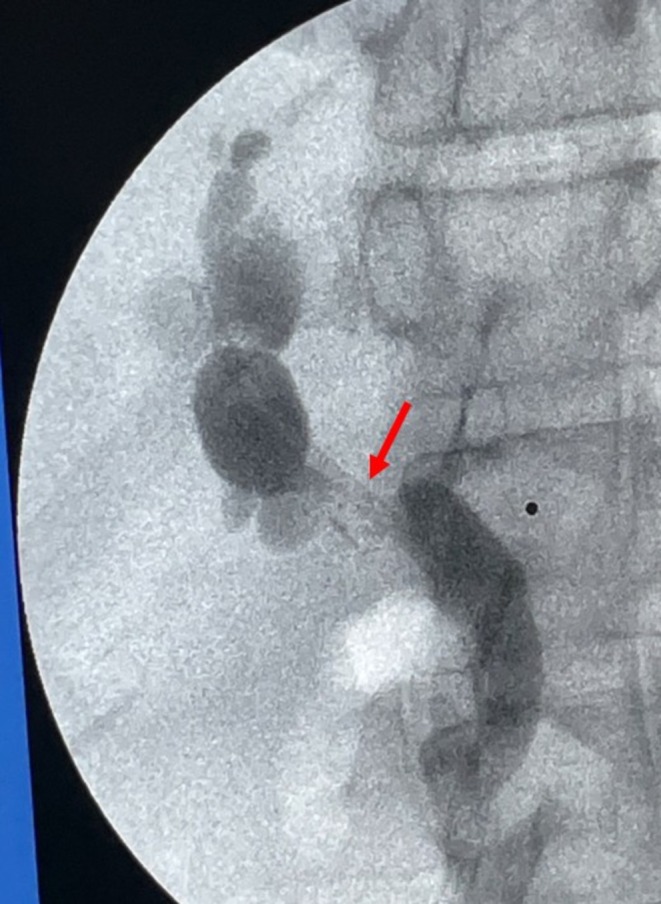

To proceed with TG‐ERCP, the roux limb and gastric remnant were both identified and dissected. The gastric remnant was mobilized, and an abdominal wall incision was made in the upper left quadrant above the left extension of the Mercedes incision. A gastrotomy was made, and a 15 mm trocar was placed through it into the gastric lumen, as previously described (Figure 2) [ref. 14]. The anterior wall of the remnant was then stammed to the abdominal wall with a 3–0 barbed suture. The abdominal cavity was temporarily closed, and overlying drapes were placed, allowing access solely to the 15 mm trocar (Figure 3). The advanced endoscopist then cannulated the trocar with the side‐viewing endoscope, and an ERCP was performed in the usual fashion (Figure 4). A single biliary stricture was identified at the anastomosis, and a 10 cm, 7‐French plastic stent was placed across (Figure 5). No balloon dilation of the anastomosis was performed due to the recentness of the anastomosis. The trocar and the overlying drapes were removed, and a 24‐French gastrostomy tube (G‐tube) was placed through the gastrotomy for future biliary access and enteral nutrition, if deemed necessary. Liver biopsy was performed that demonstrated marked canalicular cholestasis and bile ductular proliferation consistent with the biliary obstruction. There was no evidence of rejection.

Our single‐center favorable experience with TG‐ERCP is consistent with the current literature around non‐OLTx patients, which notes high success rates of 90%–100% for management of biliary postoperative pathology [ref. 9, ref. 13]. Unfortunately, in the setting of OLTx and RYGB, there is limited literature evaluating biliary interrogation techniques with this method. Given our experience and literature review, we suggest TG‐ERCP is a viable first‐line approach under certain circumstances (Figure 6). TG‐ERCP uses a single port through remnant gastrotomy, which allows for minimal dissection, reducing surgical trauma and avoiding the recently reconstructed portal triad [ref. 18]. It eliminates the higher risk of graft vascular injury by PTC drain placement, particularly in patients with nondilated bile ducts, as well as PTC contraindications of ascites and compromised coagulation [ref. 12, ref. 19]. It overcomes BAE’s lower rate of successful biliary complication management, largely confounded by the challenge of standard cannulation of the intact papilla in RYGB patients [ref. 9, ref. 20]. Further, TG‐ERCP can be performed acutely for potentially life‐threatening biliary complications in the setting of a surgically inaccessible hilum, unlike the two‐staged EDGE procedure that requires approximately 2 weeks of transluminal tract maturation in most instances [ref. 21]. In addition, utilization of the TG‐ERCP placed G‐tube is a solution to future biliary access needs and the requirement for postoperative stent removal. Furthermore, it has the capability to address malnourishment by enteral supplemental nutrition. Finally, TG‐ERCP appears to be a simple procedure in single‐center experiences, after gastric remnant access is established, given the widespread modern adoption of ERCP. In fact, this has the potential to allow for minimization of center‐to‐center variability by lowering both expertise and technological performance thresholds [ref. 10, ref. 13, ref. 18].